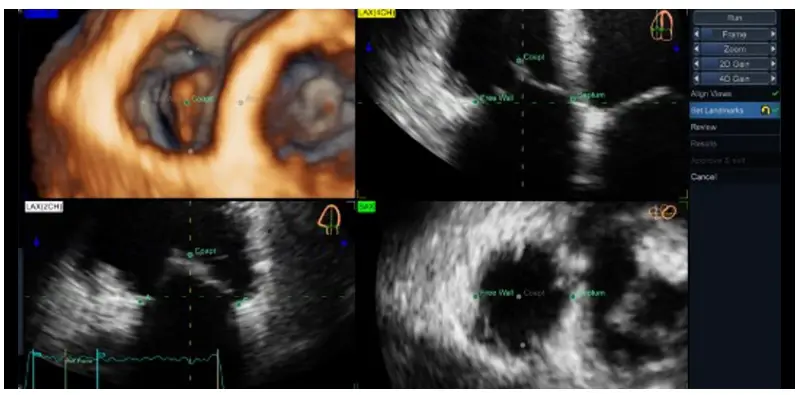

On the chosen reference frame, place the following landmarks of TV on 4CH and then on 2CH:

Free Wall (lateral free wall annulus point) → Septum (septal annulus point) → Coapt (leaflet coaptation point) on 4CH, then → A (anterior annulus point) → P (posterior annulus point) on 2CH (Figure 5).

The last click will automatically run the segmentation process. N.B. In case of uncertainty regarding the orientation of A and P points, note the corresponding position (red dot) of the landmark on the rendered SAX3D image (Figure 6) or on the SAX view plane, i.e. if it is close to the RV posterior wall, the landmark should be the P and the other one close to the RVOT is the A.

Figure 6. Illustration of the identification of landmarks of the TV using 4D Auto TVQ tool on a transthoracic data set - Figure 7. Illustration of the identification of landmarks of the TV us ing 4D Auto TVQ tool on a transesophageal data set, where the identification of A and P is more challenging on the 2CH plane. In this example, one may note the position of the P landmark and the corresponding red dot either on the SAX3D (when the landmark is above to the TA plane, white arrow) and/ or on the SAX when the landmark is close to the TA plane.